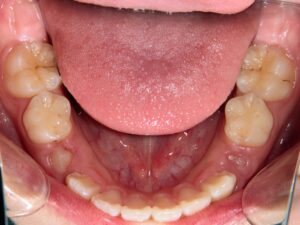

第2期治療開始時

顔貌写真

口腔内写真

開始年齢

13歳

主訴(患者様のお悩み)

残りの歯のデコボコを治したい

診断

上下顎軽度の叢生(上下の歯のデコボコ)

上顎右側犬歯低位(右上の八重歯)

治療方針

非抜歯矯正治療

全体的に装置を装着し、歯のデコボコや咬み合わせを治療

使用装置

表側矯正装置

治療期間の目安:約1年~1年半(保定期間を除いた期間)